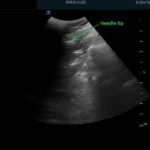

Bedside ultrasound with the transducer placed on the posterior right shoulder revealed an anterior dislocation of the right humerus. This is evident by displacement of the humeral head further away from the posteriorly placed ultrasound transducer, and appears deep to the glenoid cavity. In a posterior shoulder dislocation, the humeral head would appear closer to the transducer (and the near field of the ultrasound image) than the glenoid. Note that a hypoechoic, heterogeneous fluid collection is within the joint space, compatible with a hematoma. A right shoulder X-ray confirmed the anterior dislocation with no evidence of fracture. Under direct ultrasound guidance the glenohumeral joint space was injected with 10 mL of 2% lidocaine as an intraarticular anesthetic block. The right shoulder was reduced using continual traction. Post-reduction ultrasound demonstrated a successful shoulder reduction, depicted by the humeral head being relocated to its anatomical location, adjacent to the glenoid cavity, as noted on the ultrasound image. A hematoma remains present within the joint space. Successful shoulder reduction was further confirmed by X-ray. The patient’s arm was placed in a sling and she was discharged home with orthopedics follow-up.

Ultrasound guided intra-articular joint injections are best performed with the linear or curvilinear probe. With the probe on the patient’s lateral or posterior shoulder, locate the humeral head and the glenoid cavity. Determine the depth of the space and select a needle long enough to reach the cavity. Utilizing sterile technique, first place superficial local anesthetic. Then, advance the needle into the glenohumeral joint space and inject 10 to 20 mL of a local anesthetic, typically 1 or 2% plain lidocaine. An increase in anechoic space may be visible as the anesthetic is injected. The effect of the anesthetic should be active in about ten minutes.2,12